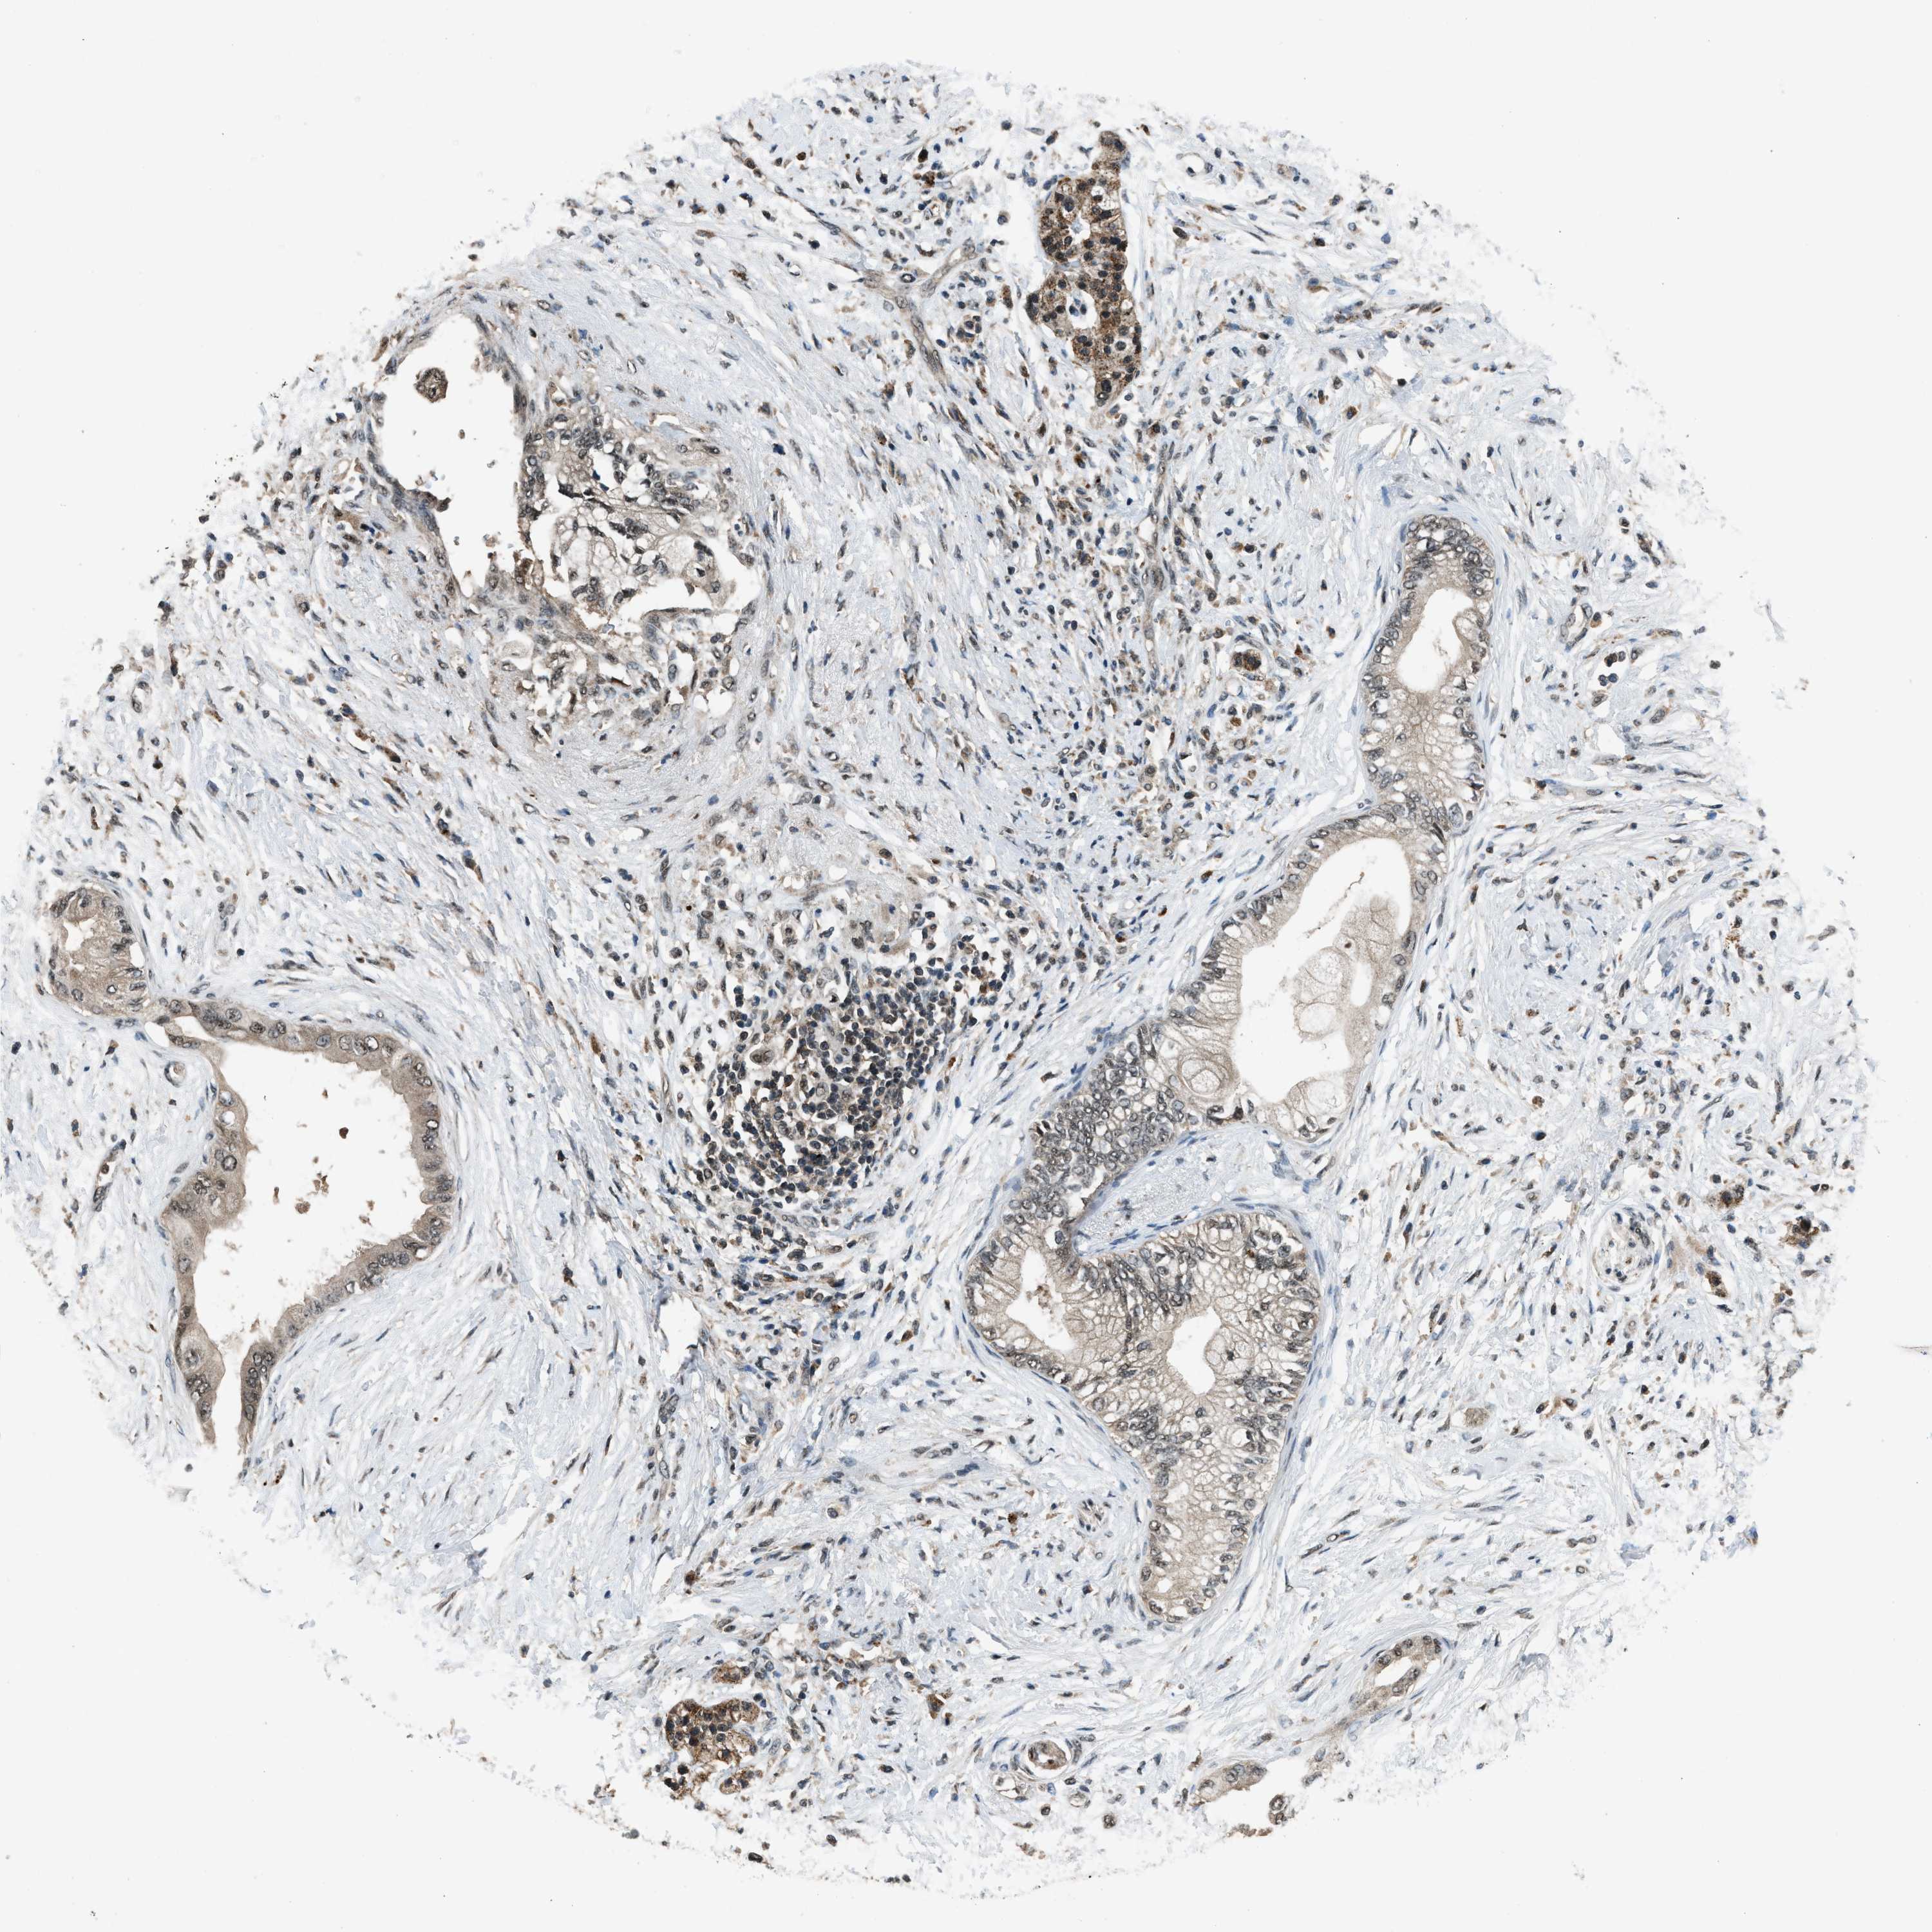

PANCREATIC CANCER - Protein expressioni

A mouse-over function shows sample information and annotation data. Click on an image to view it in a full screen mode. Samples can be filtered based on level of antibody staining by selecting one or several of the following categories: high, medium, low and not detected. The assay and annotation is described here.

Note that samples used for immunohistochemistry by the Human Protein Atlas do not correspond to samples in the TCGA dataset.

Antibody stainingi

Antibody staining in the annotated cell types in the current human tissue is reported as not detected, low, medium, or high, based on conventional immunohistochemistry profiling in selected tissues. This score is based on the combination of the staining intensity and fraction of stained cells.

Each image is clickable and will lead to virtual microscopy that enables deeper exploration of all samples and also displays staining intensity scores, fraction scores and subcellular localization as well as patient and tissue information for each sample.

Antibody HPA016713

Staining

High

Medium

Low

Not detected

Intensity

Strong

Moderate

Weak

Negative

Quantity

>75%

75%-25%

<25%

None

Location

Nuclear

Cytoplasmic/membranous

Cytoplasmic/membranous,nuclear

Adenocarcinoma, NOS